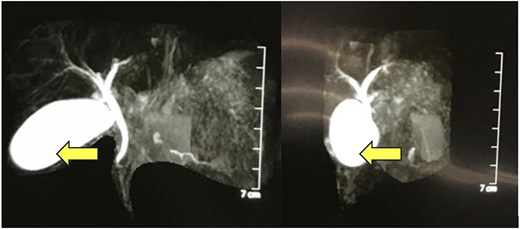

MRCP showing a thick-walled cystic lesion (arrow), anterior to the pancreas, postero-inferior to the stomach, extending up to the anterior abdominal wall, with an inner mucosal lining suggestive of a gastric duplication cyst.

A 4-year-old girl presented in September 2020 with abdominal distention for 1 month and abdominal pain for 20 days. The onset of abdominal pain was associated with repeated episodes of vomiting on a single day. There was no history of abdominal trauma or similar complaints in the past. On examination, an everted umbilicus and distended veins over the abdomen were visualized. The abdomen was tense, distended and a fluid thrill was palpable. Other general and systemic examinations were normal. Serum amylase was 1964 IU/L (normal: 40–140 IU/L). Other investigations of the patient are shown in Table 1. Abdominal ultrasound done prior to presentation in August 2020 showed a well-defined cystic mass in the left lumbar region measuring 10.6 × 12.6 × 12.9 cm (volume: 916 cc) with no septations or solid components within. The wall thickness of the cyst was 6 mm. Contrast-enhanced computerized tomography (CECT) of the abdomen showed a large thin-walled cystic hypodense lesion measuring 13 × 10.2 × 17 cm, anterior to the pancreas and compressing and anteriorly displacing the stomach, suggestive of a pancreatic pseudocyst or GDC. The maximum wall thickness was 2.3 mm and there were no calcifications, septations, or solid components within the cyst (Fig. 1). Endoscopic ultrasound (EUS) showed a large well-defined fluid collection measuring ˃17 cm replacing the entire pancreas, suggestive of a pancreatic pseudocyst. EUS-guided cystogastrostomy was done in which ⁓1.5 L of cyst fluid was aspirated and a double pigtail stent was inserted into the cyst. Post-procedure abdominal ultrasound showed a residual cyst in the epigastric regionmeasuring 9 × 9.5 × 7.5 cm (volume: 360 cc) with the drain in-situ. Post-stenting MRCP confirmed a residual thick-walled cystic lesion with air-fluid levels, anterior to the pancreas and posteroinferior to the stomach, with an inner mucosal lining suggestive of a GDC (Fig. 2). The pancreas appeared normal. She underwent surgical excision which confirmed the diagnosis of a GDC and was doing well on follow-up.